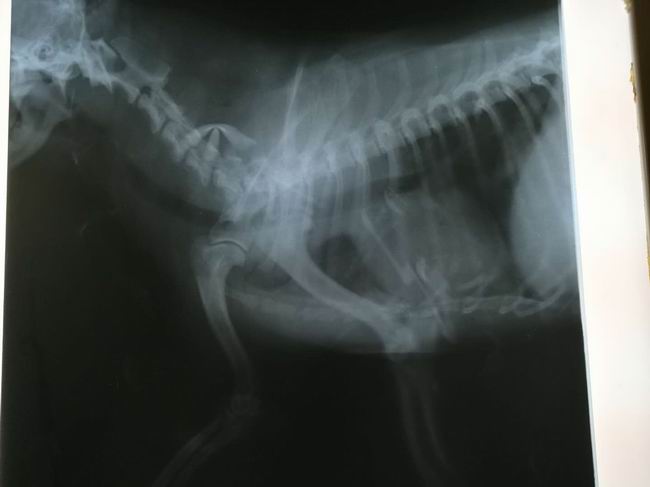

仔仔,9歲,京巴串串,平時腰椎頸椎有問題主人沒有在意,因為一次從床上跳下滑了一腳,后倒地不起四肢僵硬麻痹癱瘓,主人心急如火跑了多處動物醫院,未見起色,后來到我院經趙院長治療,每天都有很大的變化,經治療一星期都能站起來跑動。